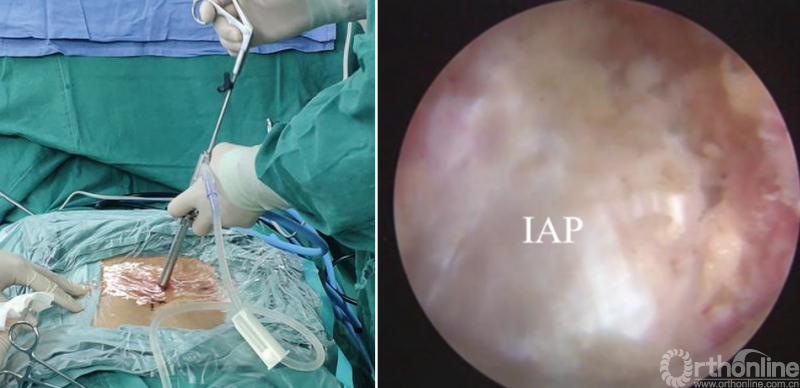

第二步“辨”:镜下辨别下关节突关节囊;

第三步“凿”:凿除部分下关节突,显露上关节突及黄韧带;

第四步“分”:分离上关节突及黄韧带;